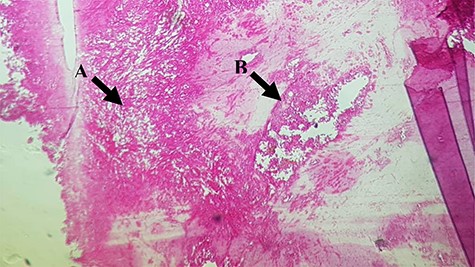

A 54-year-old female was admitted with a 6-month history of a painless abdominal mass, gradually increasing in size. She was a lifelong teacher in secondary school and has lived in one area for a lifetime, there was no asbestos-related facility. She had never been exposed to asbestos and had received an appendectomy and caesarean section, respectively, 8 and 15 years ago. She was not smoking, and her family history was negative for malignancy. On admission, she looked in a good health state, her vital signs were stable, and a movable and painless intracavitary mass was palpable over the right side of the abdomen, but ascites signs were absent. The blood count showed a white cells count of 13.100/mm3 (neutrophils 70.2%, lymphocytes 39.6%), haemoglobin of 12.4 g/dl, and platelets count of 200.000/mm3. The blood chemistry showed a creatinine level of 10 mg/l, urea 0.11 g/l and CRP < 6 mg/dl. As a result of the abdominal computed tomography scan was not sufficiently conclusive on the nature of the mass, the surgical team decided to perform an exploratory laparotomy. Laparotomy showed a localized mesenteric encapsulated and firm tissue mass weighing ~500 grams and measuring 12.5 × 10.5 × 8 cm, with no evidence of inflammation, mesenteric lymph nodes and ascites (Fig. 1). Microscopically, the tumor consisted of moderately polymorphic spindle-shaped neoplastic cells with elongated moderately pleomorphic hyperchromatic nuclei, with low mitotic activity and infiltrating connective tissue (Fig. 2). These histopathological features were compatible with a low grade sarcomatoid malignant mesothelioma. The neoplasic cells were positive with keratin AE1/AE3, CAM 5.2, and negative for desmin and CD34, which was consistent with the diagnosis. The patient has been referred to oncologist, and adjuvant chemotherapy protocol has been planned.

(A) Moderately polymorphic spindle-shaped cells with elongated moderately pleomorphic and hyperchromatic nuclei and low mitotic activity; (B) Note some layers of atypical mesothelial cells.

In histopathology examination, this mesenteric tumor consisted of moderately polymorphic spindle-shaped neoplastic cells with elongated moderately pleomorphic hyperchromatic nuclei, with mitotic activity and infiltrating connective tissue. This description is concordant with histological description of a sarcomatoid malignant peritoneal mesothelioma in the literature [4, 5]. According to literature, mesotheliomas have three basic histologic forms: epithelioid (the most frequent), sarcomatoid or mixed (biphasic) [1, 3, 5–7]. More often, areas showing features and admixtures of these three types may be encountered within a single tumor; a sarcomatoid component is observed in 25% of cases, but a pure sarcomatoid variety is extremely rare and only 32 cases have been reported in the literature since 2006 [2, 9]. Sarcomatoid mesothelioma is extremely rare: Deraco et al. [3] in a series of 49 malignant peritoneal mesothelioma reported no sarcomatoid histotypes. The immunohistopathological findings from our case were consistent with the diagnosis of sarcomatoid mesothelioma, as described by some authors [10].